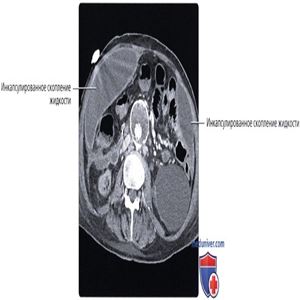

КТ с контрастированием, аксиальный срез: у пациента с сепсисом после хирургического вмешательства определяется выраженное накопление контрастного вещества брюшиной и ее уплотнение в сочетании с инкапсулированным скоплением жидкости по ходу края печени.

КТ с контрастированием, аксиальный срез: у этого же пациента определяются множественные инкапсулированные внутрибрюшинные скопления жидкости по всему объему полостей живота и таза, включая два крупных скопления, распространяющихся вниз по ходу боковых каналов брюшной полости. Брюшина, прилегающая к скоплениям, уплотнена и накапливает контрастное вещество. Сочетание этих признаков характерно для перитонита с формированием абсцесса.